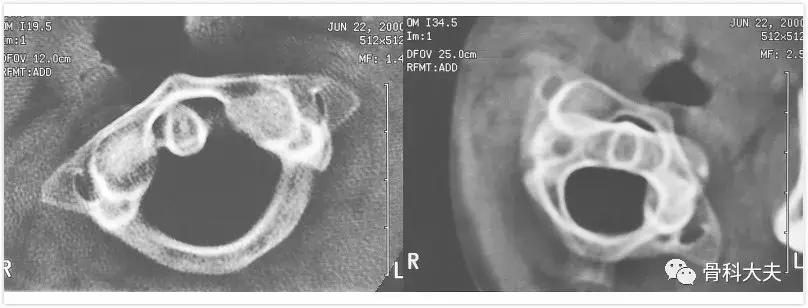

慢性脱位,未及时治疗,重建CT可看到枢椎右侧关节面继发的骨性改变

5.寰枢椎半脱位后的旋转运动:通过颈椎动态CT可以看到,寰椎左侧半脱位,头转向左侧半脱位明显,当头转向右侧后,脱位仍无法复位(如下图)。